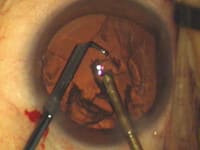

- Dr. Hoffman recommends placing the phaco needle in the eye before the irrigating instrument. He finds that makes insertion easier because there is no fluid pressure working to close the phaco-needle incision. Dr. Olson does the opposite. (See the images on pages 50 and 51.)

Bimanual Microincision Phaco: Key Steps |